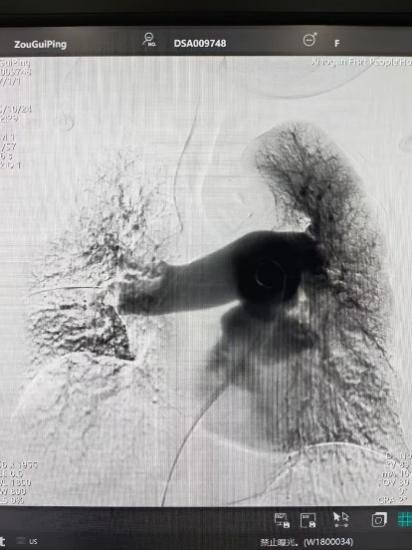

術后

手術在局部麻醉下進行,團隊通過股靜脈穿刺,將專用抽栓導管精準送達肺動脈栓塞部位,利用負壓抽吸技術成功清除大量血栓;隨后,在血栓局部精準灌注溶栓藥物,進一步溶解殘余血栓,恢復肺部血流灌注;同時,為防止下肢深靜脈血栓再次脫落引發(fā)肺栓塞,團隊為患者置入下腔靜脈濾器,整個手術歷時約1小時。術后,鄒婆婆呼吸困難癥狀即刻得到緩解,血氧飽和度顯著提升,右心負荷明顯減輕,目前身體狀況正在逐步恢復中。